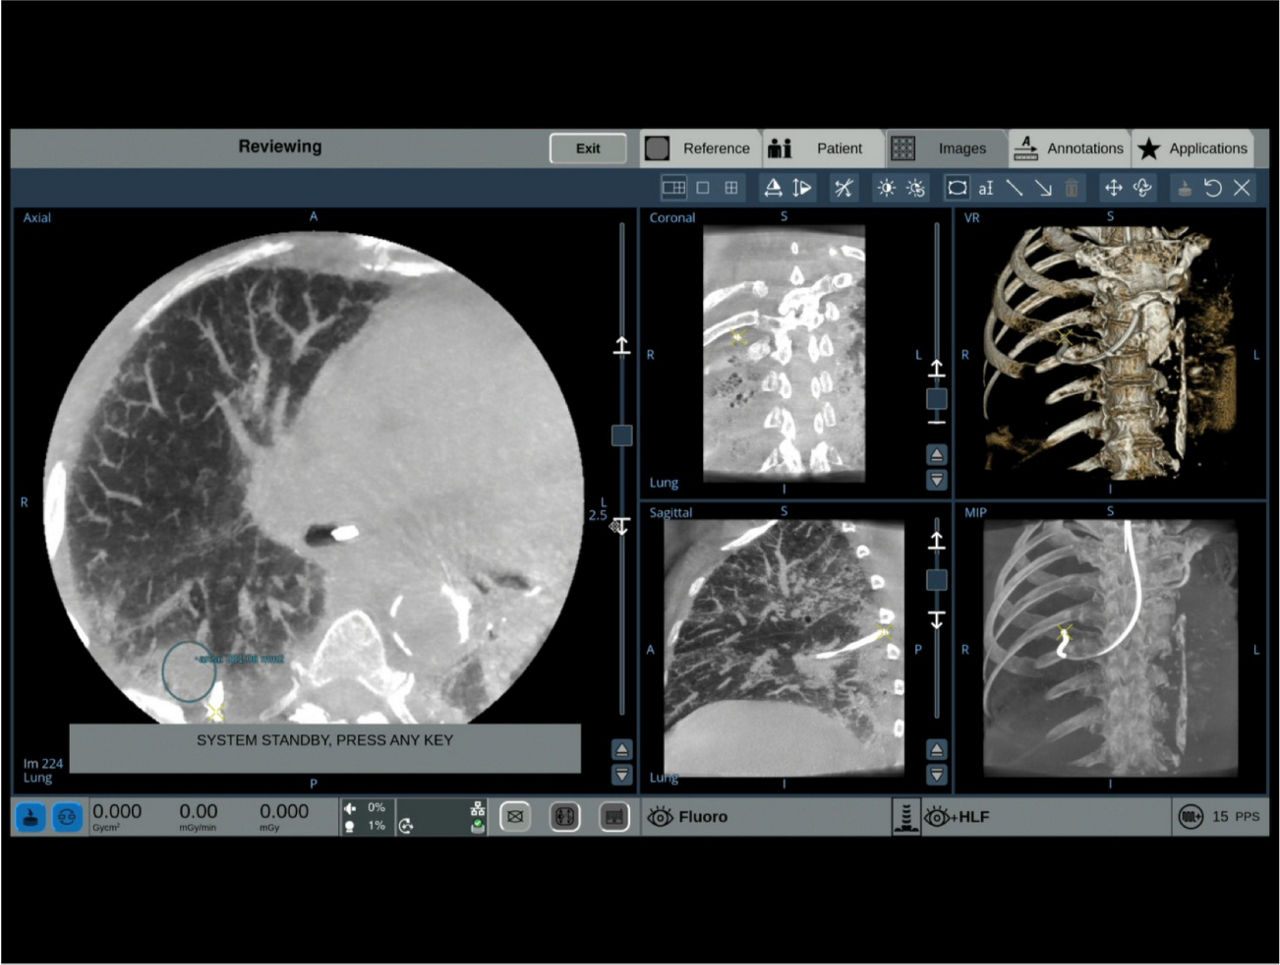

The OEC 3D provides comprehensive imaging with precise 19 cm x 19 cm x 19 cm 3D volumes and exceptional 2D images intraoperatively.

The OEC 3D presents five perspectives: Axial, Coronal, Sagittal, MIP, and VR, on a 4K display for clear and detailed review of 3D volumes and 2D images.

Select Lung Preset for optimized view of pulmonary structures. Easily change slices or adjust slice thickness for multiplanar assessment of lesions and bronchial structures.

Analyze CT-like images with the OEC 3D Volume Viewer which includes Multi Oblique Mode with reference coordinates, Window Level/Window Width, rotate, zoom, and more for quick and comprehensive tool-in-lesion confirmation.

Augmented fluoroscopy aids visualization with ability to select point of interests in the OEC 3D CBCT volume and overlay on live fluoroscopy images. To accommodate patient and equipment positioning, the OEC 3D scan range is also adjustable for a simplified imaging workflow. Features available in Lung Suite application.